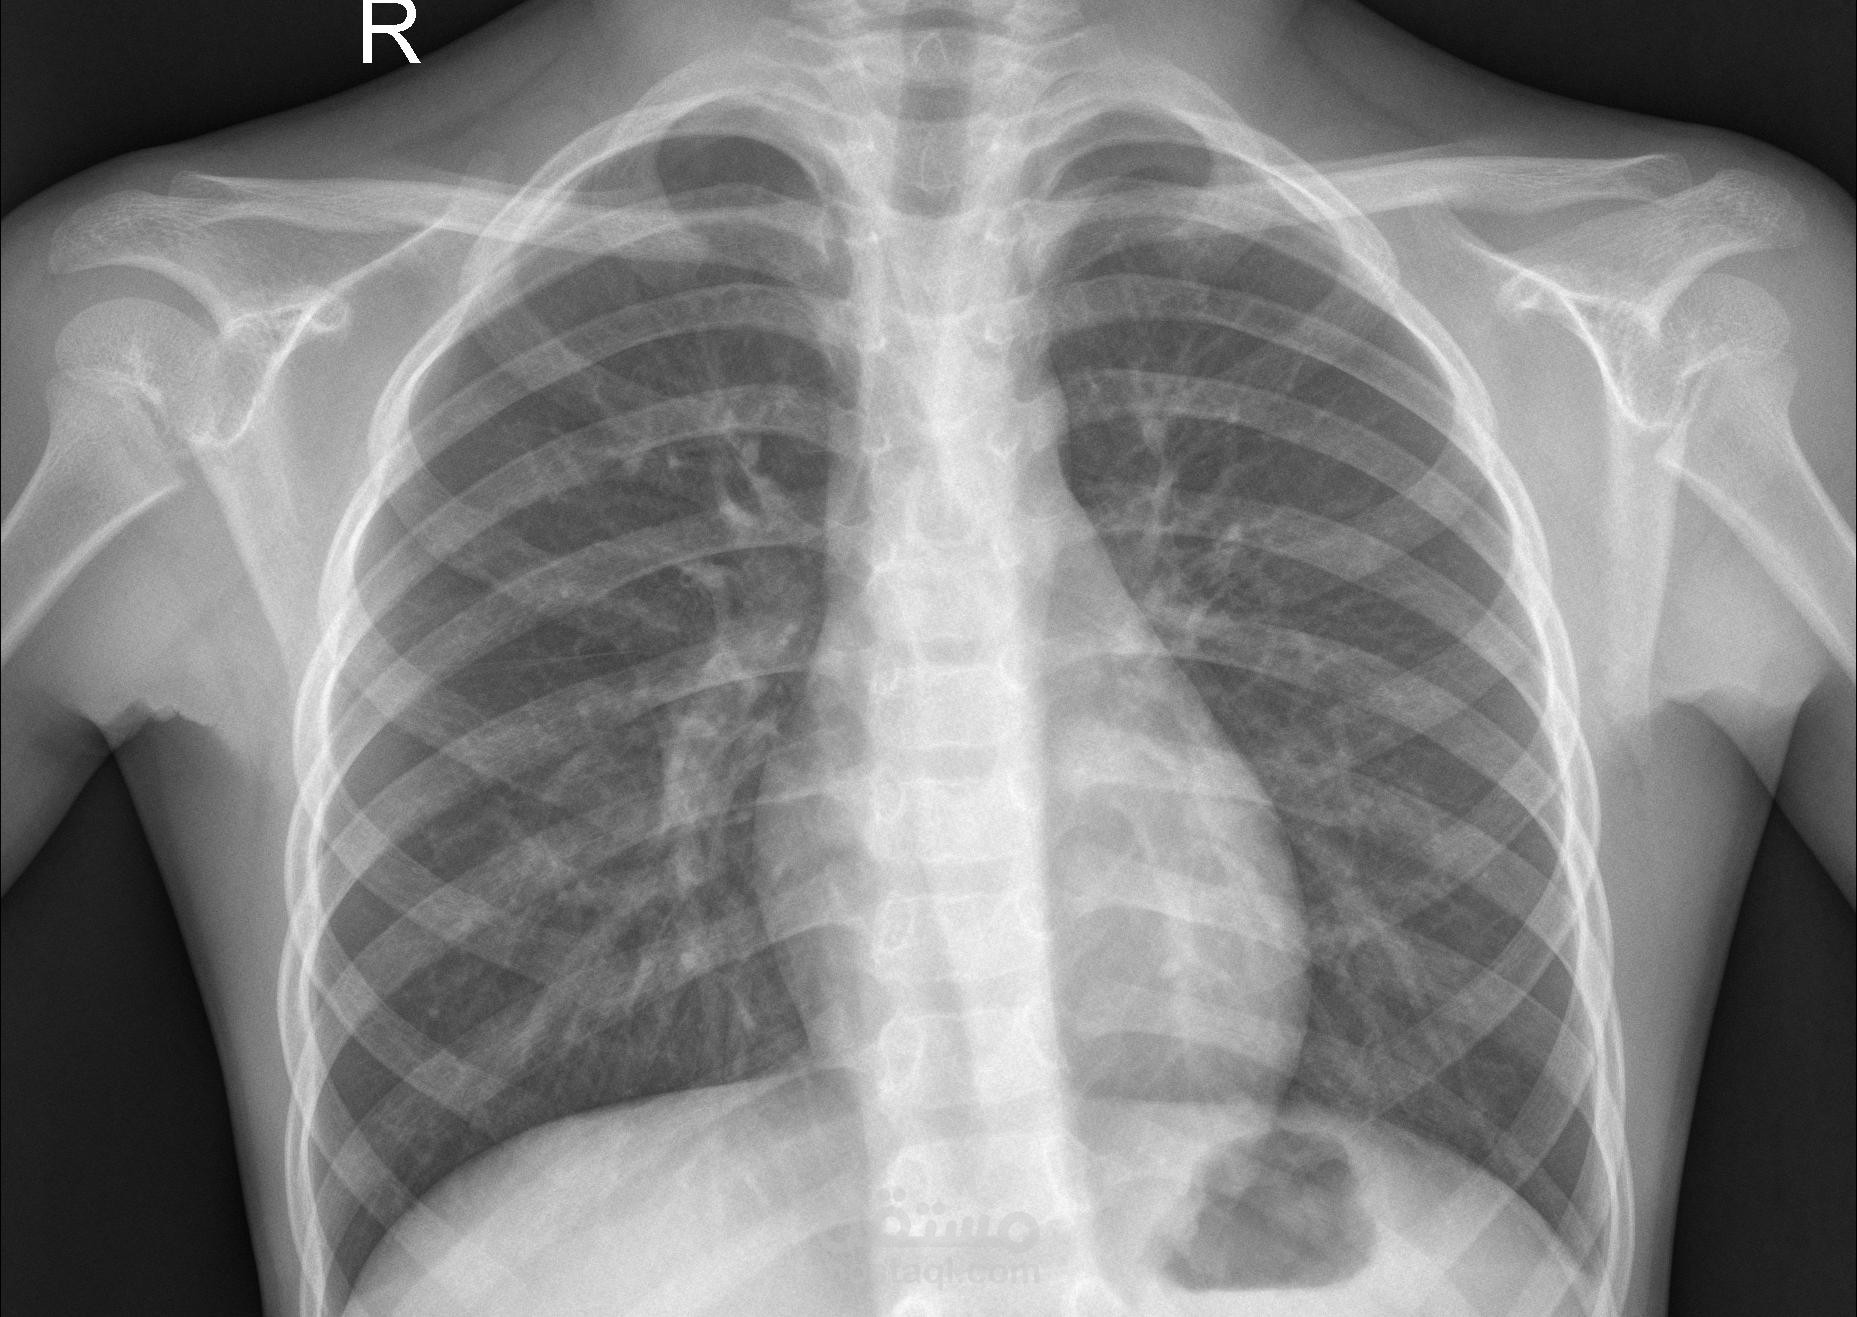

يهدف هذا المشروع إلى تطوير نموذج دقيق لاكتشاف الالتهاب الرئوي من صور الأشعة السينية (X-ray) باستخدام تقنيات التعلم العميق. تم استخدام نموذج EfficientNetB0 كنموذج أساسي، حيث أظهر أداءً ممتازًا وحقق دقة بلغت 99% على مجموعة البيانات المستخدمة. كما تم أيضًا استخدام نموذج VGG19 كجزء من عملية المقارنة والتجريب بهدف تعزيز الأداء وتحليل النتائج.

استخدام نموذج EfficientNetB0 المُدرَّب مسبقًا وتحسينه باستخدام تقنية Transfer Learning.

هذا المشروع يُظهر فعالية النماذج الحديثة مثل EfficientNetB0 و VGG19 في الكشف المبكر عن الالتهاب الرئوي، مما يعزز من فرص التشخيص السريع والدقيق في المجال الطبي.